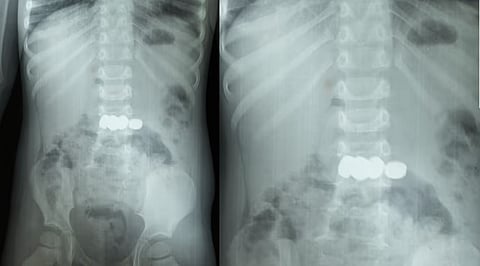

മേപ്പാടി: കളിക്കുന്നതിനിടെ അബദ്ധത്തിൽ അഞ്ച് ബാറ്ററികൾ വിഴുങ്ങിയ രണ്ട് വയസ്സുകാരനെ സങ്കീർണ്ണമായ എൻഡോസ്കോപ്പിയിലൂടെ ഡോക്ടർമാർ രക്ഷപ്പെടുത്തി. ബത്തേരി മൂലങ്കാവ് സ്വദേശികളായ ദമ്പതികളുടെ മകനാണ് അത്ഭുതകരമായി രക്ഷപ്പെട്ടത്. കുട്ടി ബാറ്ററികൾ വിഴുങ്ങുന്നത് ശ്രദ്ധയിൽപ്പെട്ട വീട്ടുകാർ ഉടൻ തന്നെ മെഡിക്കൽ കോളേജിൽ എത്തിച്ചത് വലിയ അപകടം ഒഴിവാക്കി.

ഗാസ്‌ട്രോ എന്ററോളജി വിഭാഗം സ്പെഷ്യലിസ്റ്റ് ഡോ. സൂര്യനാരായണന്റെ നേതൃത്വത്തിലാണ് ചികിത്സ ആരംഭിച്ചത്. ശസ്ത്രക്രിയ ഒഴിവാക്കി എൻഡോസ്കോപ്പിയിലൂടെ അഞ്ച് ബാറ്ററികളും സുരക്ഷിതമായി പുറത്തെടുത്തു. ഡോ. അഖിൽ, ഡോ. അഞ്ജന എന്നിവരും ദൗത്യത്തിൽ പങ്കാളികളായി.